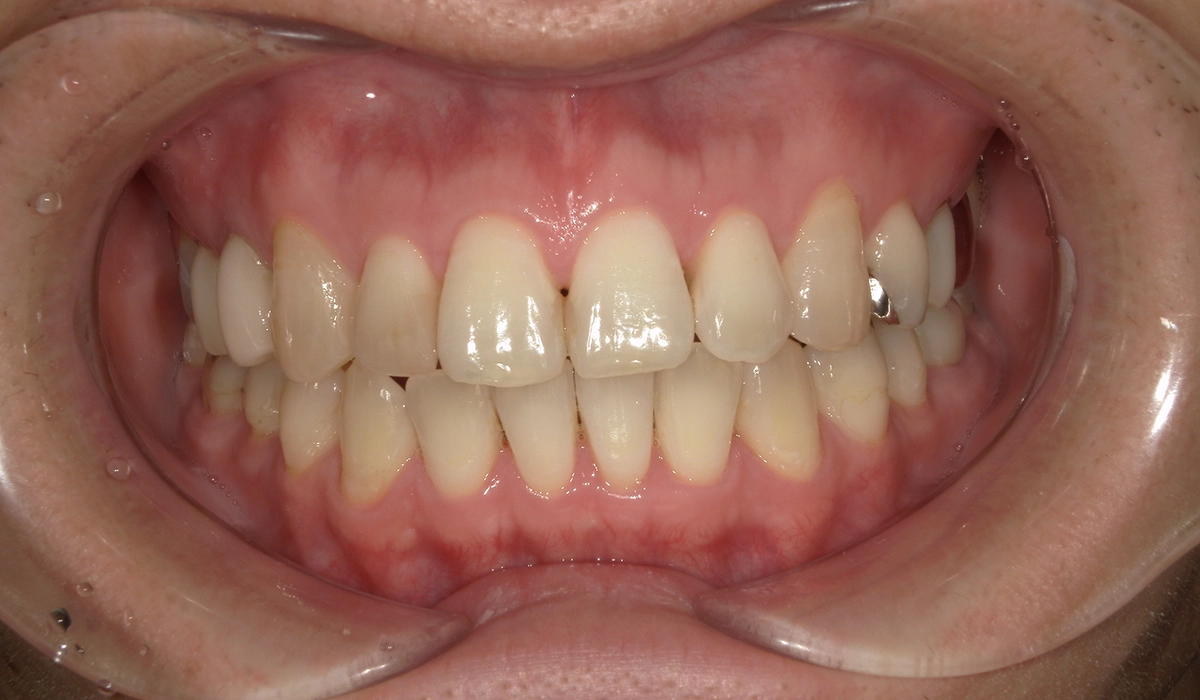

術前:正面

術後:正面